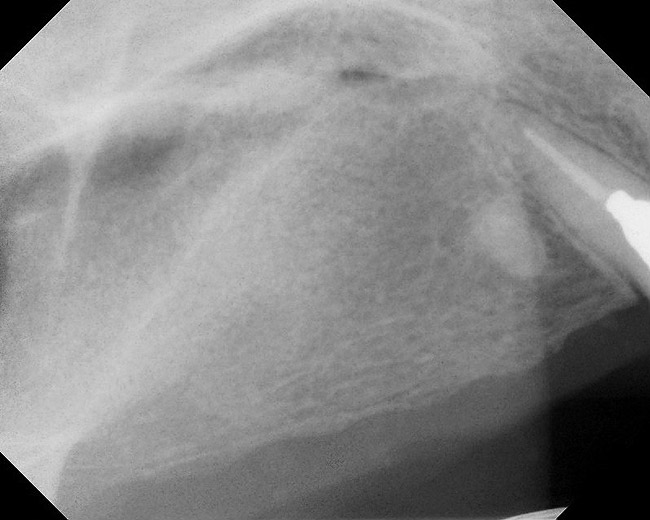

Figure 1  Buccal and radiographic views of posterior edentulism with significant sinus pneumatization in the molar region.

Figure 1

Figure 2  Buccal and radiographic views of posterior edentulism with significant sinus pneumatization in the molar region.

Figure 2